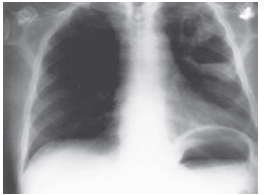

Um paciente de 48 anos foi admitido na UTI com história de uma forte gripe até uma semana atrás. Apresentava síndrome febril, tosse, dispnéia; há uma hora, apresentou hipotensão arterial. Baseado na história e na imagem, podemos afirmar o diagnóstico de: